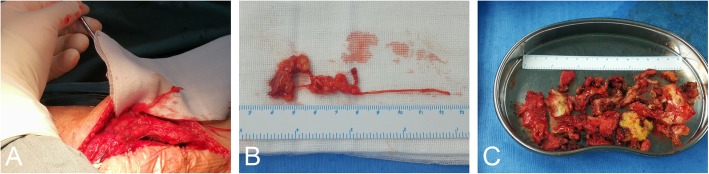

The patient then underwent right knee exploration, adhesiolysis and spacer exchange under general anesthesia. Antibiotic prophylaxis was administered for perioperative infection prevention, and the tourniquet was set at 250 mmHg. The surgery was performed through the previous surgical approach, which was a 15-cm standard midline skin incision. After blunt separation of subcutaneous tissue, we observed several thickening neuroma-like tissues distributed in both superior and inferior parts of the medial genicular area (Fig. 3a and b). Based on the innervation around the knee, these abnormal tissues may have been derived from the infrapatellar branch of the saphenous nerve or the medial femoral cutaneous nerve. Some nerve branches were scarred and adhering to surrounding blood vessels and fat in clumps. Subcutaneous neurectomy was performed and the specimen was then sent for pathological examination. The joint capsule was incised through the medial parapatellar approach. Exploration showed hyperplasia of the synovium, and the presence of a large amount of fibrous tissue around the prosthesis, patella and intercondylar fossa. The femoral component and tibial tray showed stable fixation. These findings corresponded to the stiffness of the patient’s physical examination, and confirmed the diagnosis of arthrofibrosis. Adhesion lysis was performed to remove the intracapsular scar tissue (Fig. 3c). Synovectomy was performed to remove hyperproliferative synovial tissue. The polyethylene spacer was replaced by a new one of a suitable size, with a thickness of 11 mm. The incision was then closed, and the patient’s immediate postoperative course was uneventful.

Fig. 3.

a Intraoperative photographs of the medial-sided neuroma. b Surgical neuroma specimen that was adhered to nerve, fat and blood vessel. c Scar tissue cut by adhesiolysis